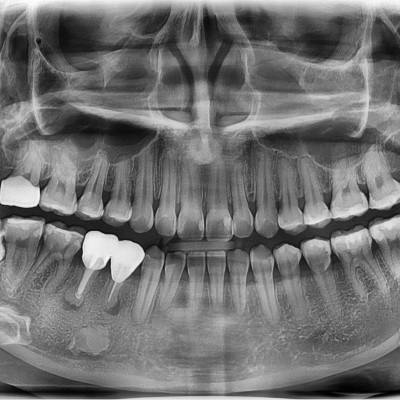

#18,28,38,48 사랑니 발치 #18,28,38,48 사랑니 발치 구강 외과 전문의가 당일 발치했습니다. ------------------..

작성자 이턱이 작성일 01-29 조회 4